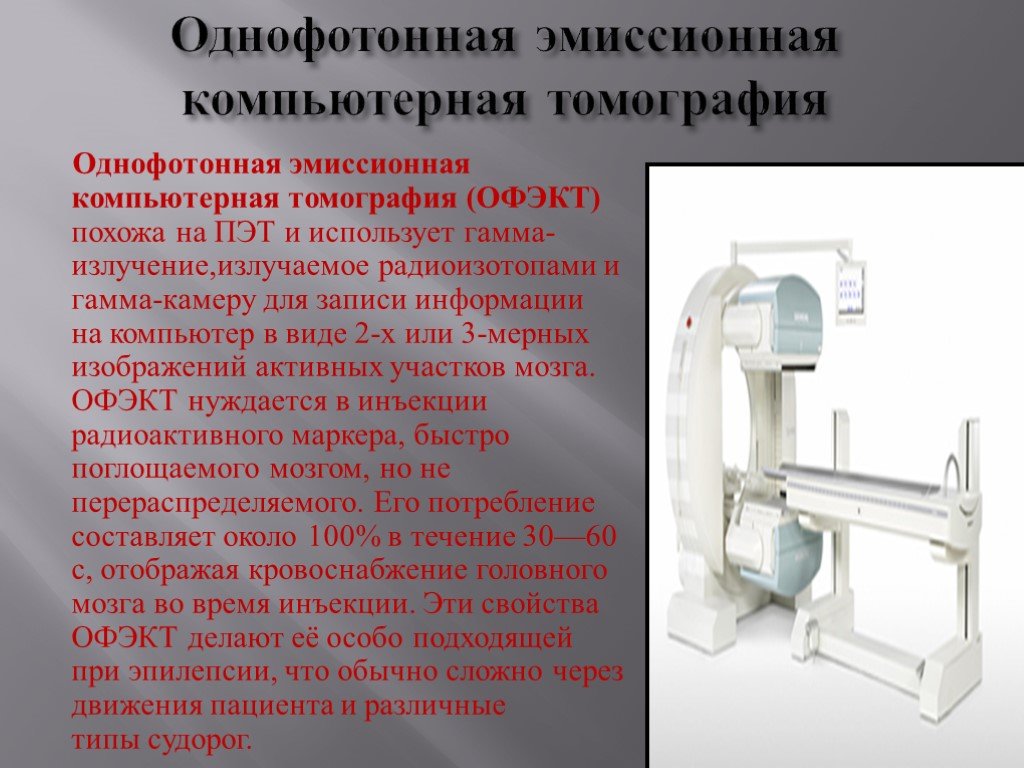

Компьютерная томография в неврологии презентация - 86 фото